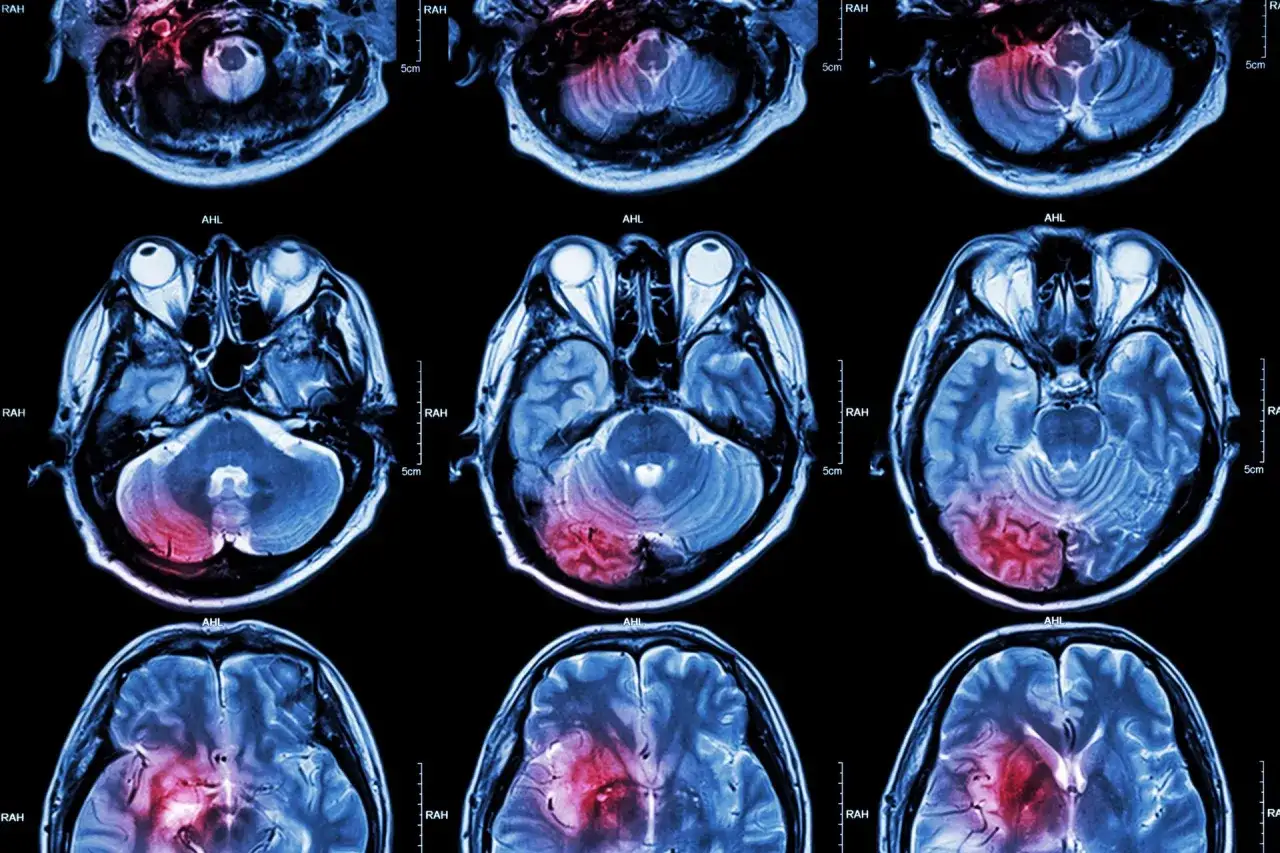

Kiedy mówimy o powrocie do zdrowia po udarze, często koncentrujemy się na widocznych deficytach. Jednak prawdziwa magia dzieje się wewnątrz naszej głowy, a konkretnie w mózgu. To właśnie jego niezwykła zdolność do adaptacji i reorganizacji, zwana neuroplastycznością, jest fundamentem, na którym budujemy proces rehabilitacji. Zrozumienie tego mechanizmu to pierwszy krok do aktywnego wspierania własnego powrotu do sprawności.

Neuroplastyczność to nic innego jak zdolność mózgu do reorganizacji. Wyobraź sobie, że Twój mózg to niezwykle elastyczna sieć połączeń. Kiedy udar uszkadza pewne obszary, mózg nie poddaje się. Zamiast tego, potrafi tworzyć nowe ścieżki nerwowe, wzmacniać istniejące lub nawet przekierowywać funkcje z uszkodzonych regionów do tych zdrowych. To właśnie ta naturalna "supermoc" pozwala na odzyskanie utraconych funkcji, takich jak mowa, ruch czy pamięć. Dzięki neuroplastyczności, Twój mózg nieustannie pracuje nad tym, aby odnaleźć nowe sposoby na wykonywanie zadań, które wcześniej były dla niego oczywiste. To właśnie na tej zdolności opiera się cała skuteczna rehabilitacja poudarowa.

Chociaż mózg jest plastyczny przez całe życie, istnieje pewien okres, w którym jego zdolność do reorganizacji jest najbardziej intensywna. Nazywamy to „oknem możliwości”. Bezpośrednio po udarze, neuroplastyczność osiąga swoje apogeum jest to czas, kiedy mózg jest najbardziej podatny na zmiany i tworzenie nowych połączeń. Dlatego też rozpoczęcie rehabilitacji jak najszybciej po zdarzeniu jest absolutnie kluczowe. Każdy dzień, każdy tydzień ma znaczenie. Im wcześniej zaczniemy stymulować mózg do pracy, tym większe mamy szanse na maksymalizację efektów terapii i odzyskanie jak największej sprawności. To właśnie w tym okresie intensywna i celowana praca przynosi najbardziej spektakularne rezultaty.